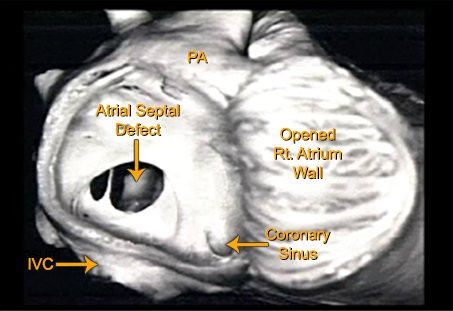

This is a pathology specimen from a patient with a secundum atrial septal defect. The large right atrium has been opened exposing a large defect. A remnant of the septum primum with two large holes is seen bridging the defect. Also seen are the inferior vena cava, the coronary sinus and the pulmonary artery

Pathology Specimen